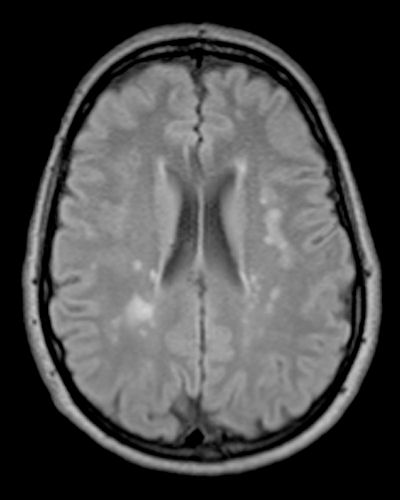

Mark the largest lesion in the scan